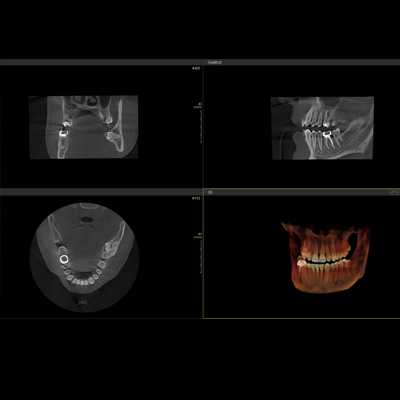

PAPAYA 3D

Diaqnostik kompyuterli erqonomik rentgen sistemi

-3D CT, Panorama

-Çoxsaylı -FOV seçimi (4×5, 14×14)

-Açıq yerləşdirmə (üzbə - üz)

-Çoxsaylı Fokuslanma

-70um görüntülü ENDO rejim